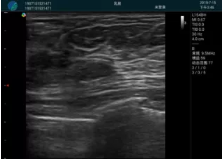

可視化穿刺引導(dǎo)

M20實(shí)時(shí)引導(dǎo):向包塊后方間隙注射利多卡因

清晰顯示腺體內(nèi)低回聲快影,邊界清晰,包膜較光滑

確定進(jìn)針路徑并實(shí)時(shí)監(jiān)測抽吸針與腫塊位置關(guān)系

抽吸針進(jìn)入腫塊內(nèi)部進(jìn)行旋切

抽吸過程中可見腫塊明顯縮小,并根據(jù)腫塊位置改變針道位置

抽吸旋切后再進(jìn)行超聲復(fù)查,原腫塊區(qū)域未見殘留組織及出血

超聲引導(dǎo)下抽吸旋切取出的腫塊組織